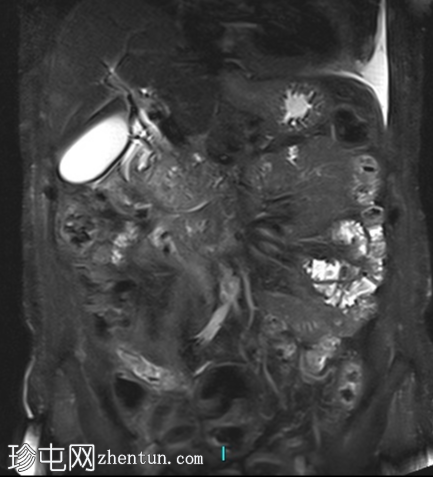

冠状位

T2加权像

胰腺钩突附近可见边界不清的肿块,T2加权像呈不均匀中等信号,弥散受限明显。肿块大小为4.1 x 5 x 3 cm(前后径 x 横径 x 头尾径)。伴有胰管扩张,直径约6 mm。

肝脏可见多个大小不一的可疑病灶(从亚厘米级到2厘米不等)。T2加权像呈高信号,弥散受限明显。

远端胆总管突然变窄,但未完全阻塞。

胰腺周围可见多发囊性病变,部分与主胰管相连,提示胰腺导管内乳头状黏液性肿瘤(IPMN)。

双侧胸腔积液,左侧较多。